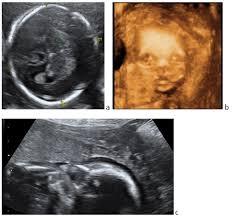

But ultrasound is not 100% accurate. The healthcare provider may also take a blood sample. Problems caused by trisomy 13 or 18 may not be seen with ultrasound. But ultrasound is not 100% accurate. However, few infants live more than a few days. Ultrasound is not 100 percent accurate, since some babies with trisomy 18 and 13 may look the same on ultrasound as those without the syndrome. The healthcare provider may also take a blood sample. A biometric measurement below the fifth percentile was noted in nearly half of cases in the second trimester. Trisomy 13 is a genetic disorder that your baby gets when they have an extra 13th chromosome. Trisomy 13 detected on cvs. During amniocentesis, a sample of fluid that surrounds the developing fetus is removed and analyzed, while cvs involves the removal of tissue samples from a portion of the placenta. Trisomy 13 is often picked up at 12 weeks with an increased nt. When ultrasound findings are consistent with trisomy 13, prenatal karyotyping should be undertaken.

Now, this doesn't mean that the abnormalities aren't there. Trisomy 13 is typically due to having three full copies of chromosome 13 in each cell in the body, instead of the usual two copies. Patau syndrome (also known as trisomy 13) is considered the 3 rd commonest autosomal trisomy. Trisomy 13 and 18 are very different in terms of what you can see on ultrasound. Trisomy 13 represents the presence of an extra chromosome 13 resulting from a free copy or translocation. When an afp test indicates a high risk for trisomy 13, usually a level 2 ultrasound (also called a targeted ultrasound) is scheduled. The screening also determines risk of patau (trisomy 13) and edwards (trisomy 18) syndromes, rare and often fatal chromosomal abnormalities. If a maternal fetal dna test result comes back as high risk for a chromosomal abnormality, the recommendation (1) is to confirm the. Greater than 90% of fetuses with trisomy 13 have findings detected on prenatal ultrasound. Targeted sonography identified abnormal fetal anatomy or abnormal biometric measurements in 95% of fetuses with trisomy 13 in the second trimester after 17 weeks' gestation. Smith et al (1999) summarized the findings of 11 cases of trisomy 13 detected on cvs, of which, three cases had confirmed trisomy 13 mosaicism in the fetus. The purpose of this chapter is to focus on the evaluation and management of isolated ultrasound soft markers diagnosed in the second trimester. Fetal ultrasound during pregnancy can also give information about the possibility of trisomy 18 or 13, but ultrasound is not 100 percent accurate because some babies with trisomy 18 and 13 may look the same on ultrasound as those without the syndrome.

Trisomy 13 is a genetic disorder that your baby gets when they have an extra 13th chromosome. In the united states, most cases of trisomy 13 are detected prenatally, either by genetic screening or ultrasound. This is because each a. The healthcare provider may also take a blood sample. The nt ultrasound is done between 11 and 13 weeks, when baby's nuchal translucency, the clear tissue located at the back of a developing baby's neck, can be measured.